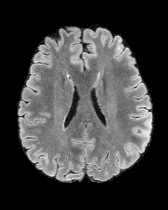

We also test our approach on healthy samples. Ideally, we would like our generative process to act as the identity function when given a normal image as input. Some examples are shown in Figure 6, where we can observe that the changes introduced by our sampling technique are relatively minimal and Dif-fuse preserves the structure and general appearance of the images.